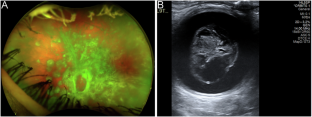

The first patient had bilateral choroidal metastases and unilateral vitreous cells (treated with external beam radiotherapy and immunotherapy), the second had unilateral amelanotic vitreous metastasis (treated with vitrectomy and BRAF-MEK inhibitors) and the third had bilateral multifocal choroidal metastases (treated with BRAK-MEK inhibitors followed by immunotherapy). The fourth patient (previously reported) had unilateral anterior segment and vitreous metastases (treated with immunotherapy and enucleation). Interestingly, two patients had a history of uveitis in the affected eye, unrelated to the ocular metastases. All four patients had synchronous systemic metastases.